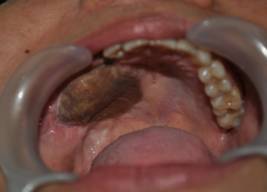

INTRA ORAL IMAGES

OCCLUSION REHABILITATION